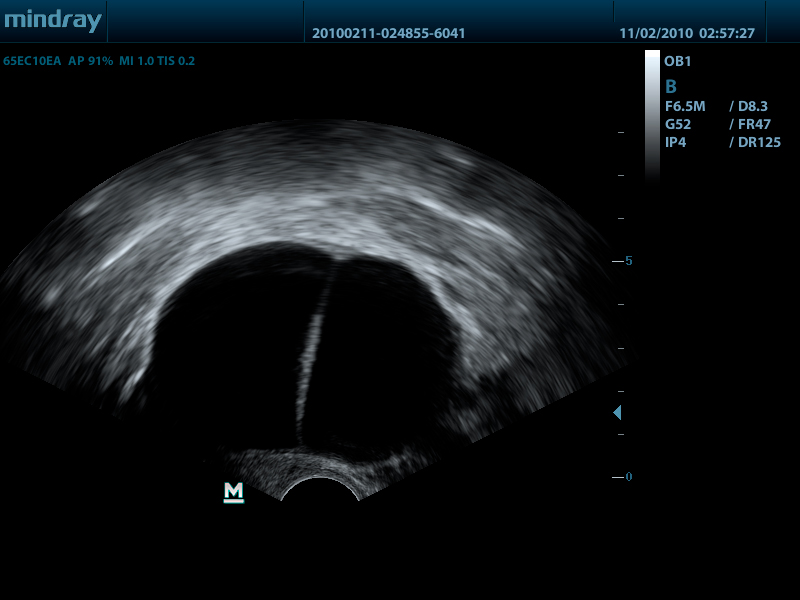

- Внутриполостной датчик 65EC10EA, 3.0 - 12.5 МГц, радиус кривизны 10 мм